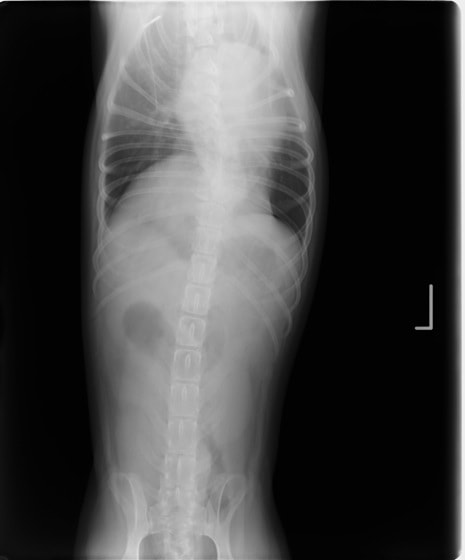

■ 症例1 2歳、柴犬、去勢雄

主訴:発咳の頻度増加、努力性呼吸

各種検査結果

・ 血液検査:異常なし(TG:167mg/dL、Tcho:115mg/dL)

・ 胸部レントゲン検査:胸水貯留

・ 心エコー検査:異常なし

・ 胸水の性状:乳白色、TP:5.4g/dL、SG:1.038、TG:>500mg/dL、Tcho:65mg/dL、小リンパ球・好中球主体、細胞数:少ない

・ CT検査(リンパ管造影):無気肺以外の異常なし

レントゲン画像